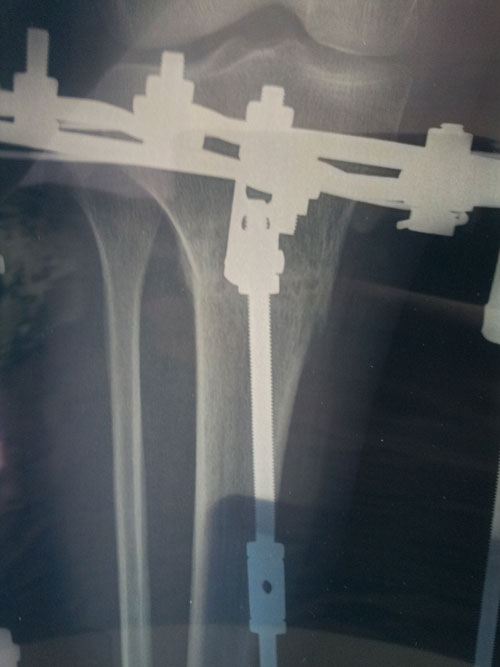

Рентген в 59 дней

Напоминаю:рентгеновские снимки делать на одной плёнке (вначале прямая проекция, затем боковая проекция), чтобы видеть ось.

Когда фотографируете R- снимки, не закрывайте опознавательные буквы (где левая, а где правая голень?)